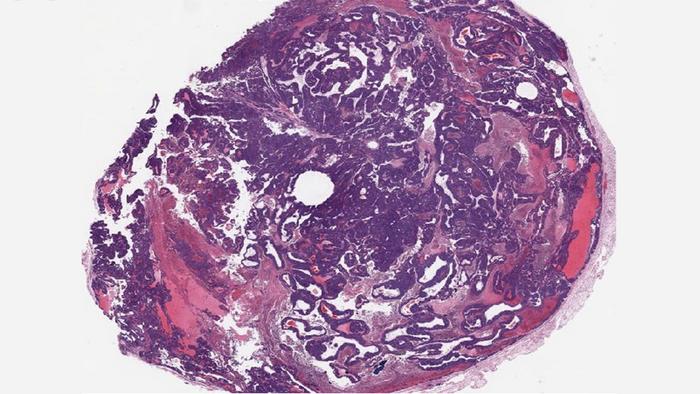

BPTF knockout tumor (IMAGE)

A mammary tumor from a BPTF knockout mouse; animals with lower levels of this protein had fewer cancer metastases and lived longer than those with normal BPTF levels.